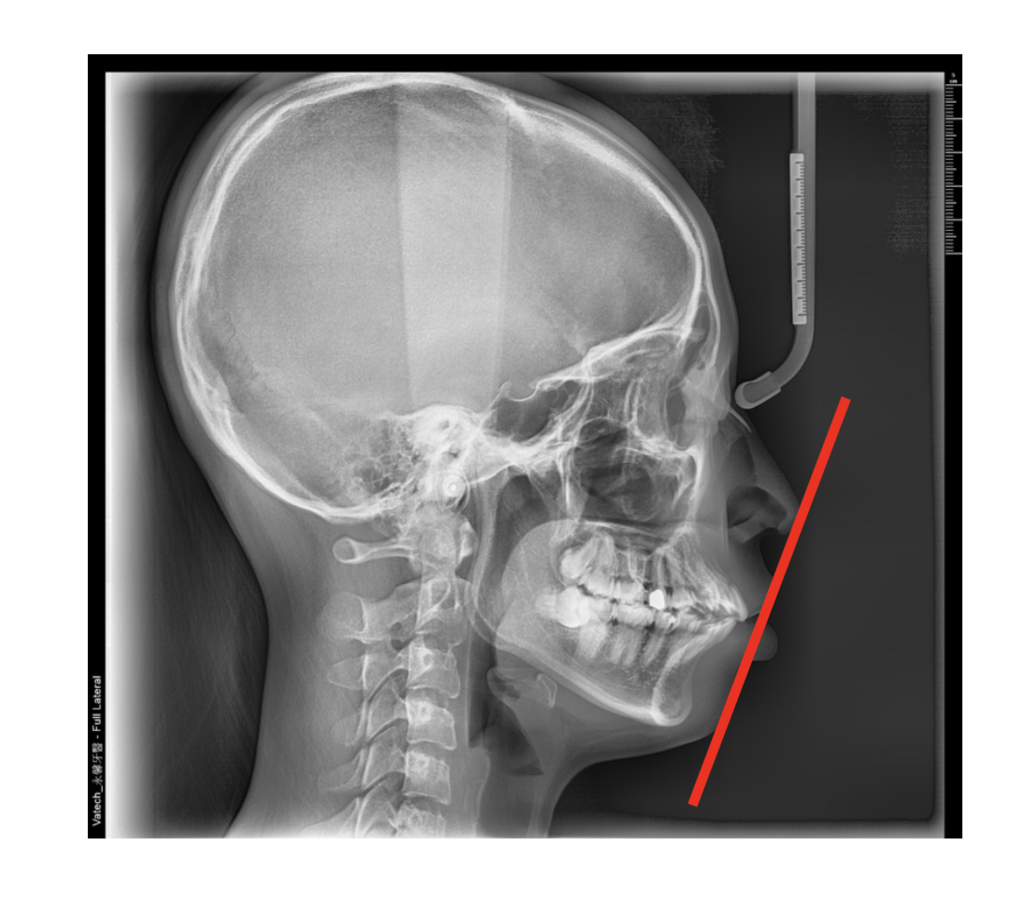

側臉的輪廓我們常用從鼻尖到下巴最突點的連線 - 美觀線來做為參考基準

亞洲人上下嘴唇的位置剛好落在美觀線上或略往內的臉型較為理想

「牙齒矯正」牙齒矯正可以讓臉變小嗎?高雄牙醫推薦